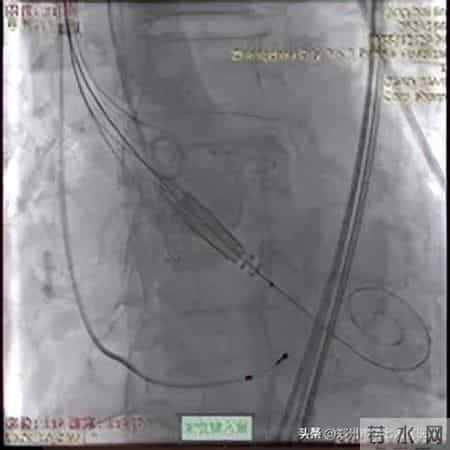

在充分的术前准备之后,手术的大幕正式拉开。在手术过程中,张申伟教授精准操作J-VALVE TF系统,通过股动脉路径微小切口,在“自主导航定位系统”引导下,将人工瓣膜准确输送至病变部位。在释放瓣膜的关键环节,他凭借对系统性能的深刻理解和娴熟的操作手法,精确调整瓣膜位置和角度,确保瓣膜与自体瓣环完美贴合。整个手术过程紧张有序,最终成功完成瓣膜置换。术后,患者心脏功能得到明显改善,第二天即下床活动,最终顺利康复出院。